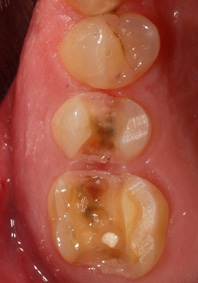

Ablauf einer Cerec-Rekonstruktion: 1. Zustand bei Behandlungsbeginn  CEREC-Verfahren; Schritt 2: Vorbereitung durch Entfernen der alten Füllung und Kariesentfernung  CEREC-Verfahren; Schritt 3: dreidimensionale intraorale Digitalisierung   CEREC-Verfahren; Schritt 4: Aussehen nach Befestigung der Kauflächen auf der ZahnsubstanzWorkflow einer komplexen Vollkeramikrekonstruktion in nur einer Sitzung